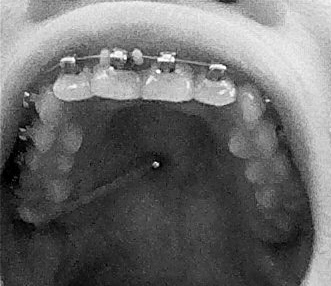

經過兩個禮拜的折磨

舌頭終於比較習慣骨釘和磨人的矯正線

被割出的大裂縫雖然還沒全好,但也好一半啦~